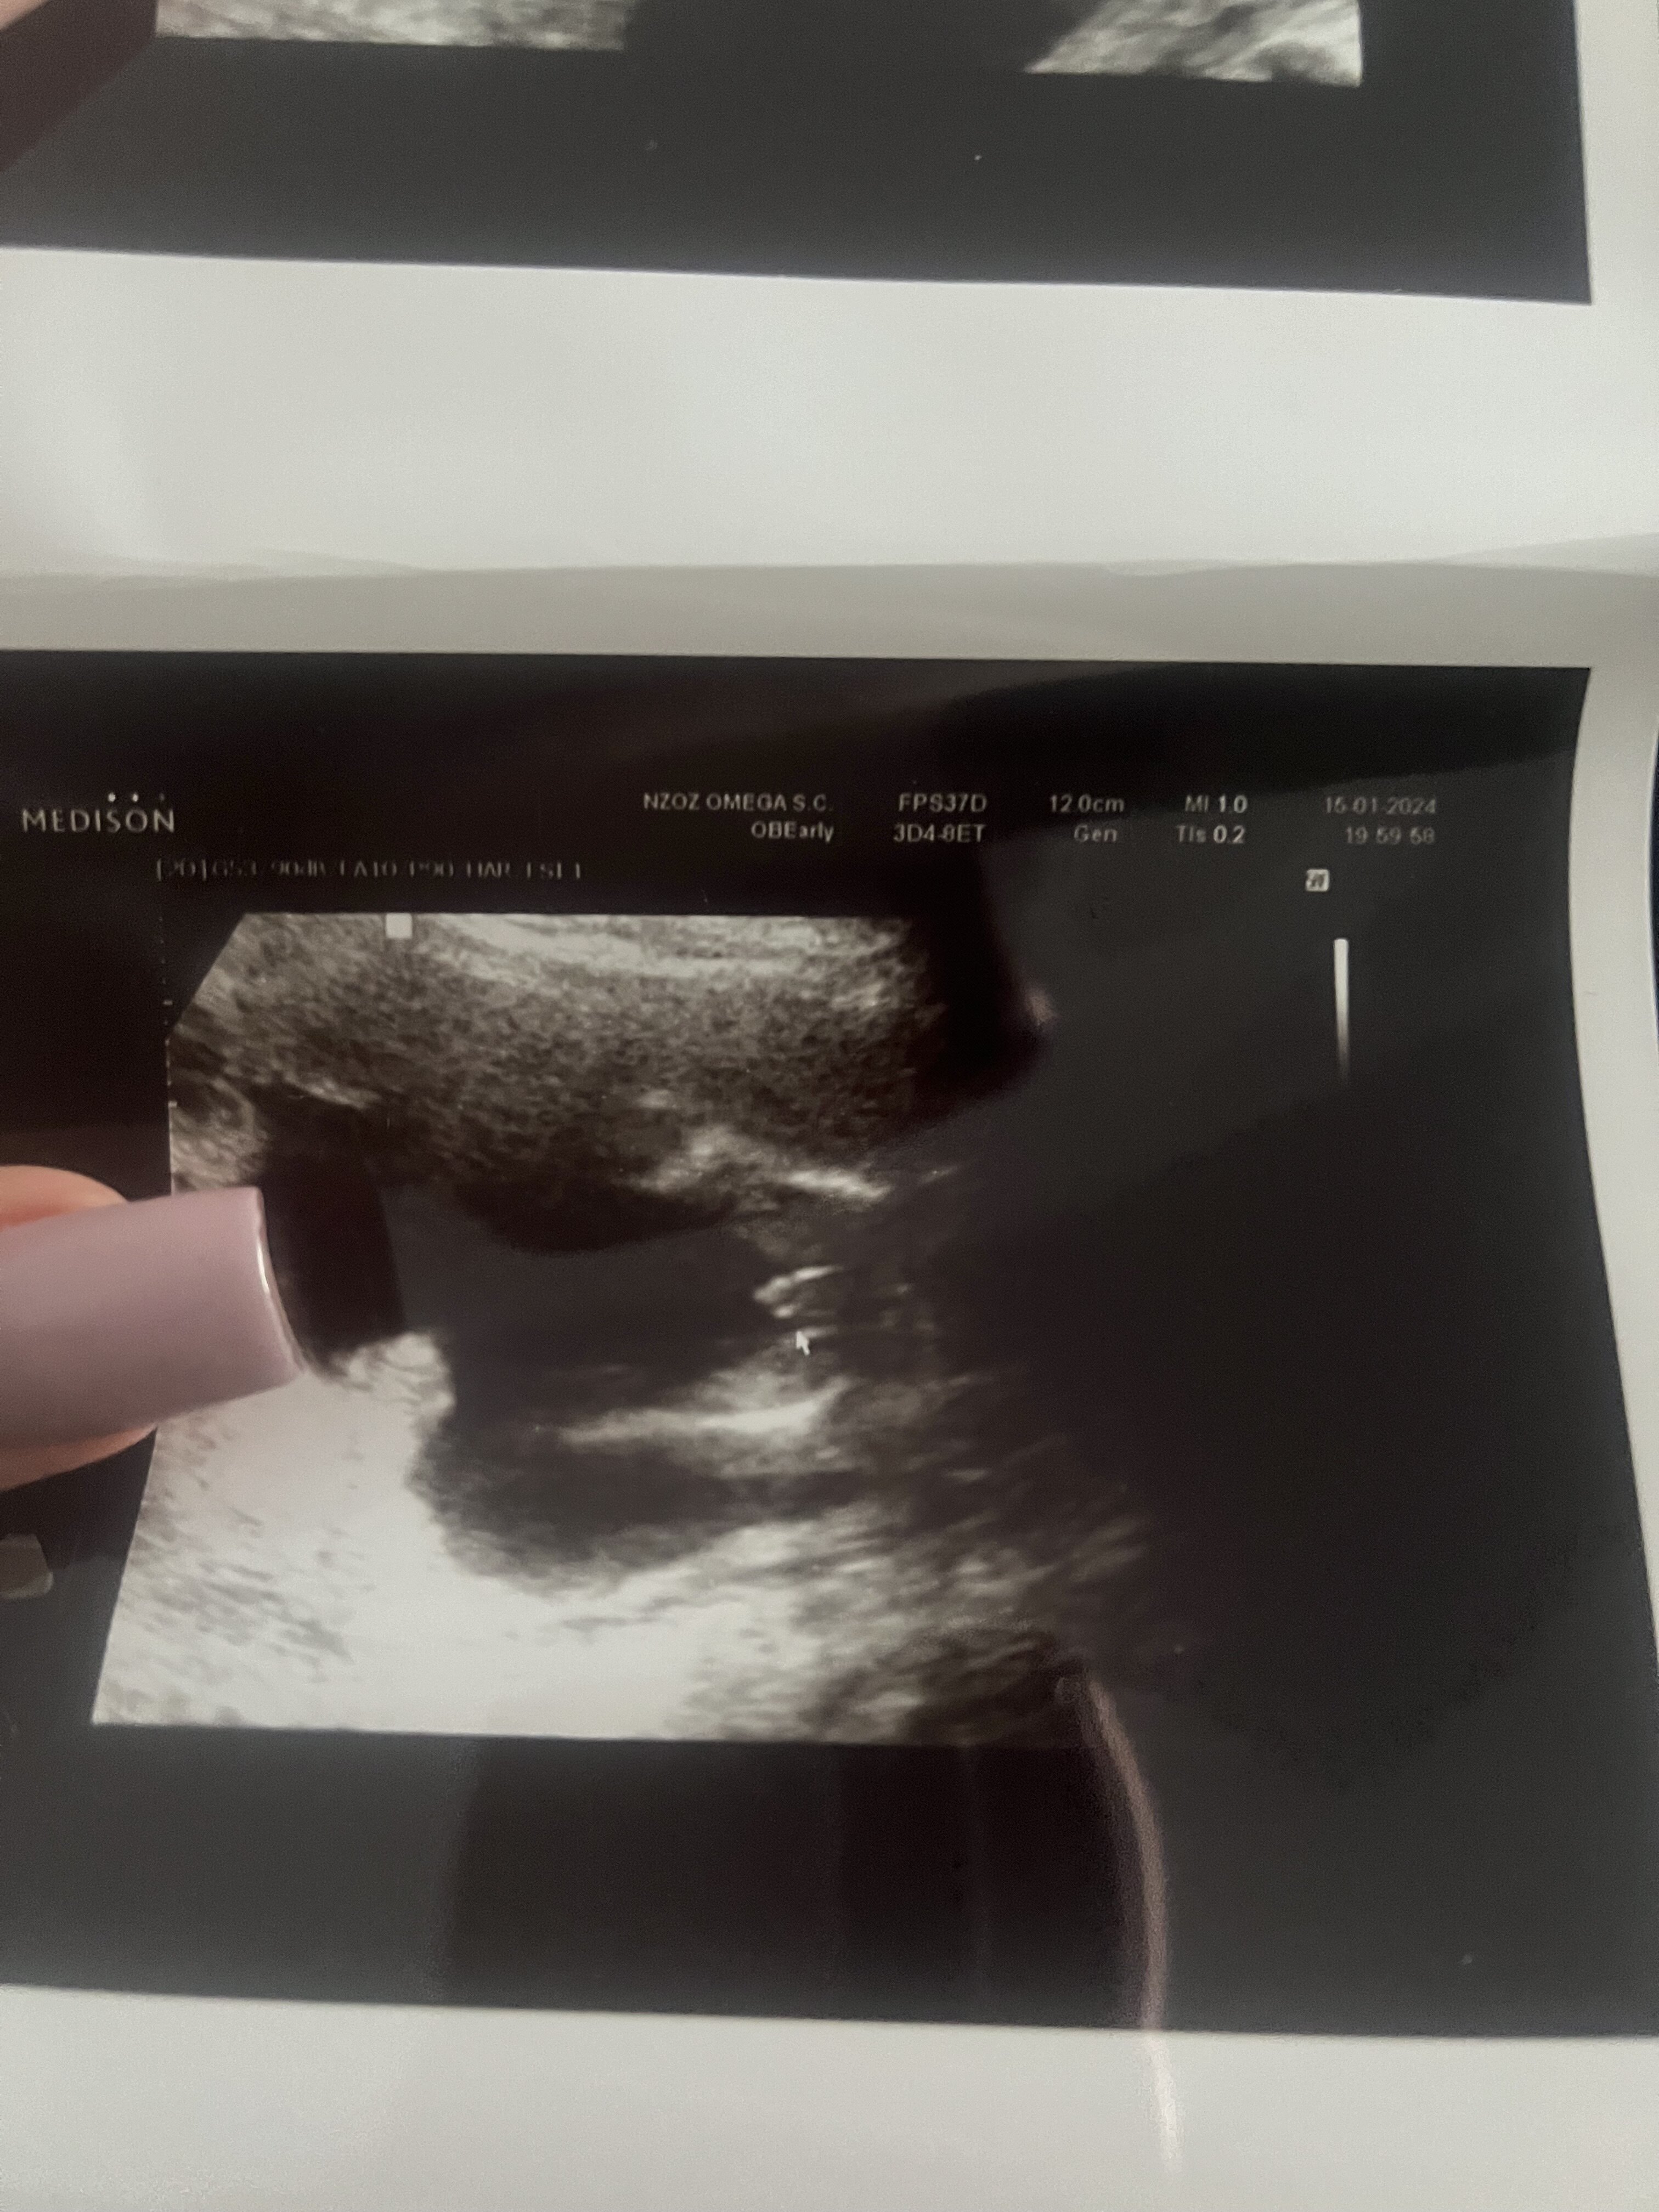

Dla mnie to typowy chłopakCześć kochane, chciałam tylko poznać wasze zdanie odnośnie co Wy widzicie na zdjęciu ? Kto się nam kryje w brzuszku , bo zdania są podzielonepozdrawiam Zobacz załącznik 1605105

Tak , jeden lekarz twierdzi że to może być jeszcze wyrostek lub wystające wargi sromowe a inny , że właśnie jajeczkaDla mnie to typowy chłopakZdania lekarzy też podzielone? Ja idę jutro u nas sprawdzić przy okazji kontroli

Jeśli to miałby być wyrostek, to trzeba też zobaczyć z boku w przekroju, bo z nocnikowego ujęcia to bardzo trudno określić. My w 15+4 jeszcze mieliśmy wyrostek, teraz idę jutro 17+2 i zastanawiam się czy nie będzie jakiegoś niejasnego obrazu USGTak , jeden lekarz twierdzi że to może być jeszcze wyrostek lub wystające wargi sromowe a inny , że właśnie jajeczkai mamy taką zagwozdkę

na zdjęciu również 15+4 tcJeśli to miałby być wyrostek, to trzeba też zobaczyć z boku w przekroju, bo z nocnikowego ujęcia to bardzo trudno określić. My w 15+4 jeszcze mieliśmy wyrostek, teraz idę jutro 17+2 i zastanawiam się czy nie będzie jakiegoś niejasnego obrazu USGKtóry to tydzień na zdjęciu? Wargi sromowe to bardziej trzy kreseczki albo taka bułeczka, tutaj to tego nie przypomina według mnie